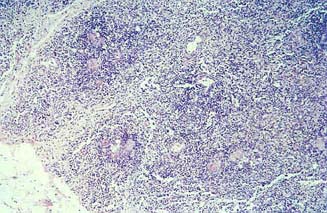

Timo-Atrofia

TIMO-ATROFIA: Atrofia tímica en la que se ha perdido la zona de la corteza (linfocitos T).